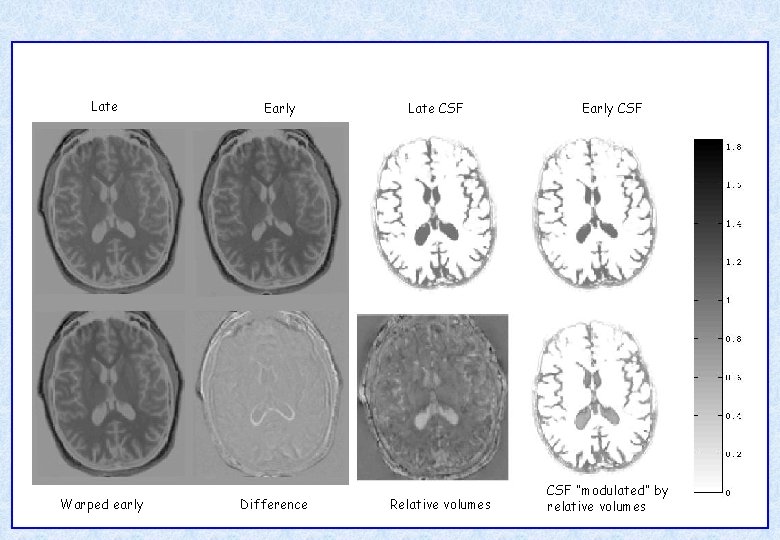

Late Warped early Early Difference Late CSF Relative volumes Early CSF “modulated” by relative volumes